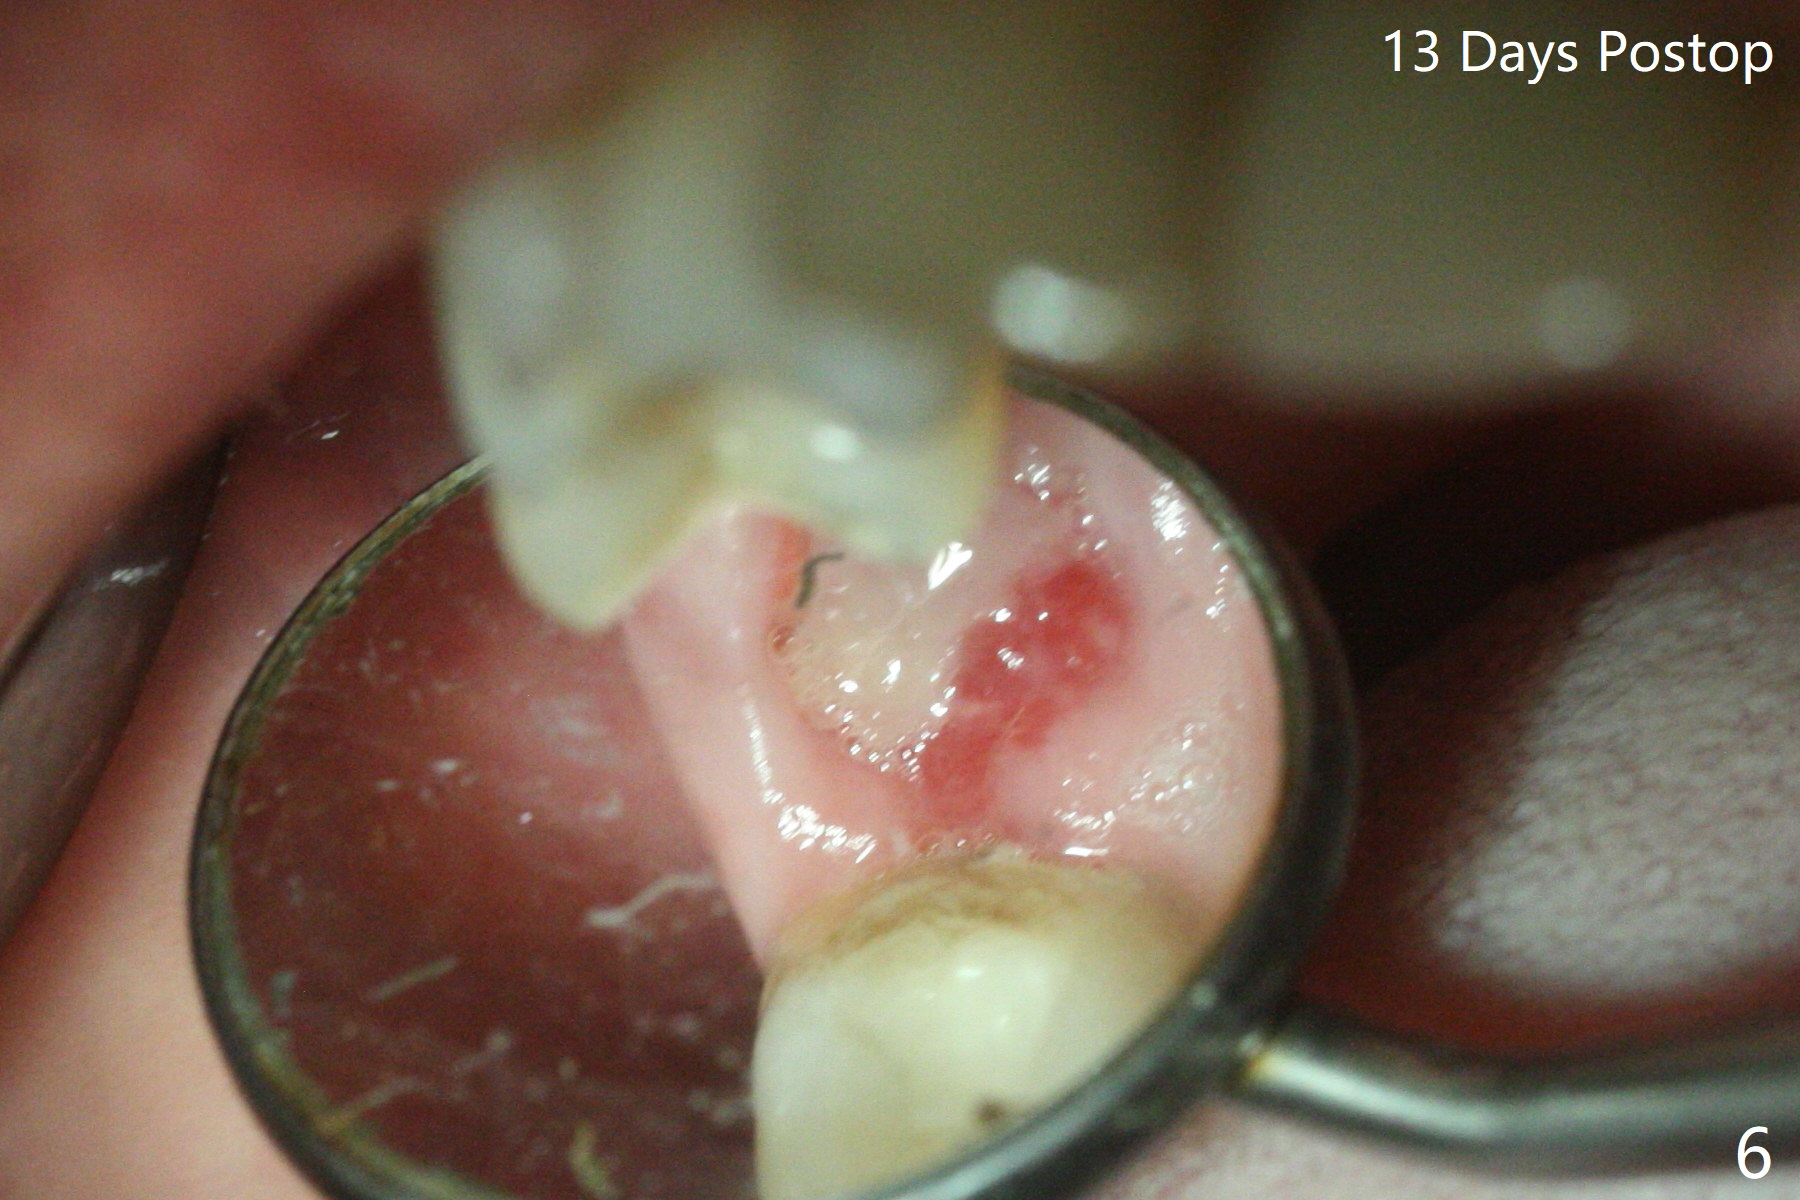

A 53-year-old woman wants to extract the tooth #3 with recurrent apical periodontitis (Fig.1). Socket preservation is conducted (Fig.2). The tooth is terminal in the arch and difficult to keep periodontal or acrylic dressing in place. To overcome the situation, a prefabricated space maintenance is placed without cementation because of its inherent fitness (Fig.3). Periodontal dressing (Fig.4 D) appears to be retained in place. The spacer is lost prematurely due to no cement, but the wound appears to be healing 13 days postop (Fig.5,6). The socket heals 3 months postop (Fig.7,8). However the ridge is narrow 19 months postop (Fig.9, as compared to that of the tooth #14 (Fig.10)).